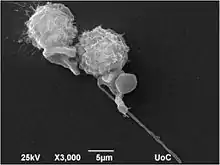

Medications, such as fosbretabulin (a type of combretastatin), bortezomib and TNF-Related Apoptosis Induced Ligand (TRAIL), are, however, under investigation in vitro and in human clinical studies. Based on encouraging Phase I and II clinical trial results with fosbretabulin,[8] a type of medication that selectively destroys tumor blood vessels, clinical trials have been evaluating whether the medication can extend the survival of patients with ATC.[9]